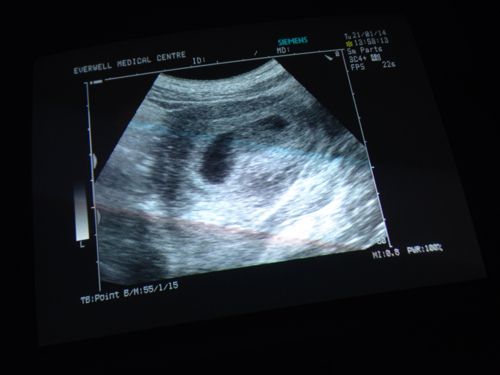

许多人很纳闷为什么生殖中心医生要求月经第二、三天做阴道B超,特别是在准备拟定温和刺激、微刺激、拮抗剂等促排卵方案前,更是每个病人都要求先行B超检查后再定促排卵方案,现在告诉大家原因吧!

在月经第2、3天做阴道B超我们可以了解:

二、基础窦卵泡数目

女性的生育能力和卵巢中的卵泡数有关。在月经第2、3天通过B超来了解您卵巢的窦卵泡的数目,这样我们可以评定卵巢的功能,如果每边窦卵泡数>12枚,我们就高度怀疑患者有多囊卵巢的倾向,那么在制定促排卵方案时就要减少促排卵药的使用剂量,避免有OHSS(卵巢过度刺激)的风险。如果每边的窦卵泡数<4枚,我们要警惕患者有卵巢功能衰退的趋势,结合患者的具体情况给出下一步受孕治疗计划。

在月经第三天,我们还可以了解卵泡的大小,如果卵泡直径>10mm,说明本周期卵泡已经提前募集(提前生长),这时就不需要再用促排卵治疗了,改为自然周期或加大促排卵药物的剂量,免得卵泡生长的参差不齐。在月经期做B超我们还可以了解卵巢内有无上周期没有排出的残留卵泡,如果上周期的卵泡没有排掉,使用了促排卵药可能会影响它的萎缩,同时干扰了新卵泡的发育。如果在第三天没有做B超了解卵巢的情况,有可能在促排卵期将上周期的残余卵泡当成本周期新发育的卵泡从而影响治疗。